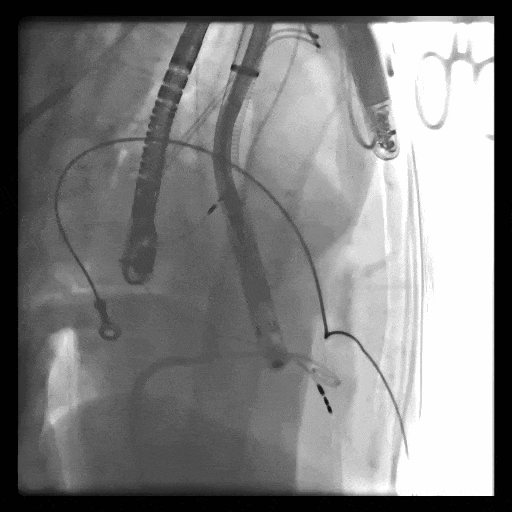

術中DSA顯示起搏器導線的干擾,右心室造影確定瓣環(huán)位置,操作空間小